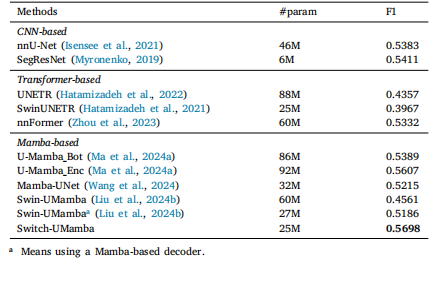

Table 3Results of cell segmentation on the Microscopy dataset. For a fair comparison,the Swin-UMamba results are reported without the benefit of ImageNet-basedpre-training.

表3 显微镜数据集上的细胞分割结果 为保证对比的公平性,所报告的Swin-UMamba模型结果未借助基于ImageNet的预训练(优势)。